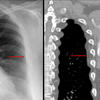

Aortic nipple

Ex 1 CT

Date: 03/23/2004

Views: 5343